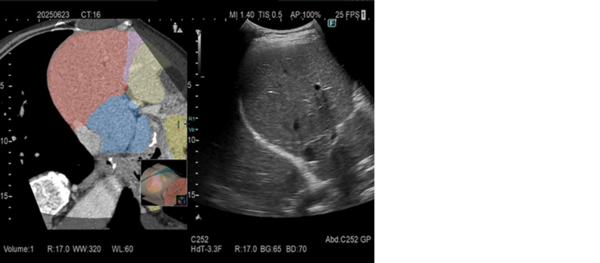

(3)Real-time Virtual Sonography(RVS)*3*4

RVSは,超音波画像と他モダリティ画像をリアルタイムに並列表示する機能。超音波検査だけでは発見しづらい小さな病変の発見や,治療部位の決定など安全かつ正確な治療への貢献が期待される。「ARIETTA 850 DeepInsight x」「ARIETTA 750 DeepInsight x」は,RVSによる検査開始時のボリュームデータ検索や,バーチャル像と超音波画像との位置合わせを自動化し,操作手順を低減した。検査者の習熟度を問わず簡単に使用することが可能で,検査の短時間化も期待できる。

また,CT/MR画像などのバーチャル像の情報から領域を分類して超音波(US)画像に重ねて表示することが可能。これにより,描出部位の位置関係をわかりやすく可視化し,検査をスムーズに進めるとともに,ワークフローの効率化によって検査時間の短縮が期待される。

▲ 造影CTデータの輝度解析により領域分類された参照画像をバーチャル像上へ重畳表示